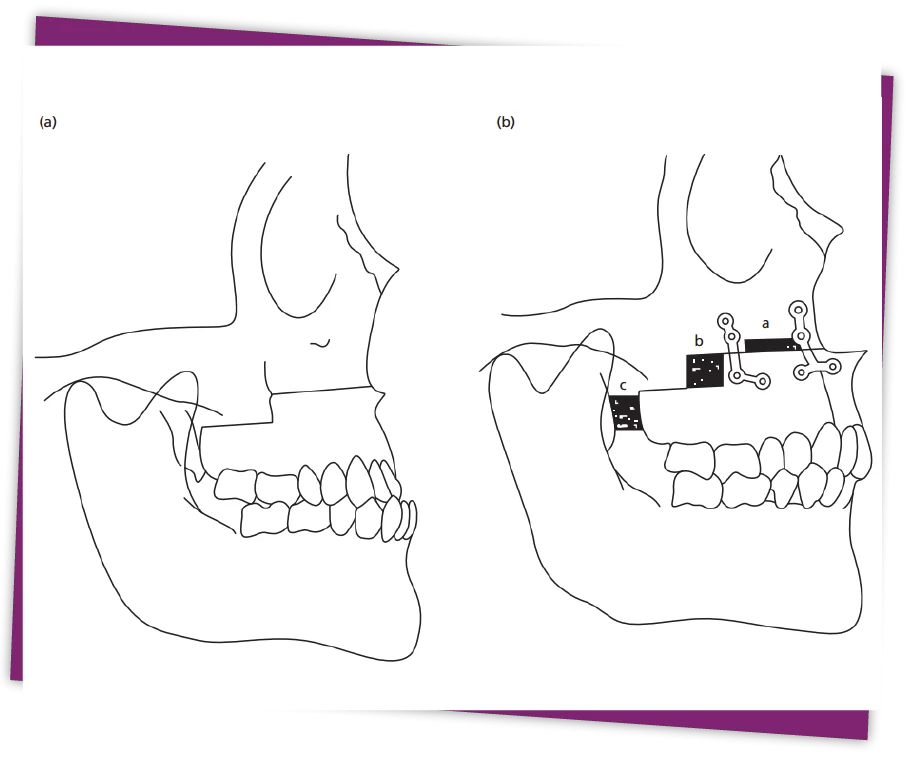

Bác sĩ sẽ dùng thiết bị máy cắt xương chuyên dụng để tác động đến phần xương, cắt đẩy lùi hàm dưới về sau có thể kết hợp kéo xương hàm trên về phía trước để làm khít khớp cắn.

Nếu móm mức độ trung bình: Phẫu thuật cắt xương hàm dưới trượt về sau (phương pháp BSSO) để làm khít khớp cắn.

Nếu móm nặng, hai hàm xa nhau quá nhiều: Phẫu thuật cắt xương hàm dưới đẩy lùi về sau (BSSO) và cắt chỉnh xương hàm trên kéo đưa về phía trước (Phương pháp Lefort I).

Sau khi chỉnh sửa vị trí tối ưu của 2 hàm, xương được cố định lại bằng nẹp vít cứng chắc, mang đến sự cân đối cho hai hàm, khớp cắn khít nhau, hỗ trợ việc ăn nhai.